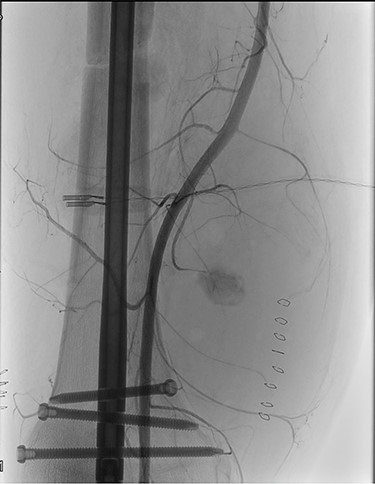

Completion angiography demonstrated the patency of the femoro-popliteal axis and of the tibial vessels (Fig. 3). Anterior and posterior fasciotomy of the leg was performed. At the end of the procedure a CW-Doppler was made showing triphasic-flow in the anterior and posterior tibial artery.

Completion angiography demonstrating patency of the popliteal artery, anterior tibial artery, posterior tibial artery and peroneal artery.